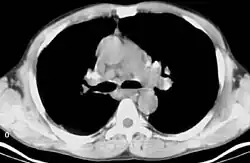

Bilateral hilar lymphadenopathy

Bilateral hilar lymphadenopathy is a bilateral enlargement of the lymph nodes of pulmonary hila. It is a radiographic term for the enlargement of mediastinal lymph nodes and is most commonly identified by a chest x-ray.